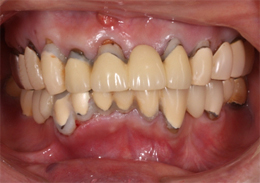

上顎のALL-ON-4②(ノーベルクリニシャンを使用したフラップレス術式)

フラップレス術式は、メスを使用しない無切開手術(フラップレス術式)です。

手術前の精密検査(CT撮影)によって顎骨の状態を正確に把握し、3Dコンピューターシミュレーション(ノーベルクリニシャン)による診断でインプラント埋入部位の詳細な治療計画が立てられるため、一般的なインプラント手術で必要となる切開・剥離・縫合のステップが省略できるため、短時間での手術が可能になります。

そして、出血もほとんどなく術後の腫れや痛みを軽減できるため、患者様の身体的負担を軽減できる低侵襲な最新のインプラント術式です。

-

- 主訴

- 歯周病で歯がグラグラするので噛めない

- 治療内容

- 上顎に残存していた歯を抜歯。歯肉の治癒後にフラップレス手術にてインプラント埋入を行い、その場で準備してあった上顎上部構造を仮歯として、ねじ固定式で装着

- 治療費用

- 上顎ALL-ON-4:4,000,000円(税別)

- 治療期間

- 6ヶ月